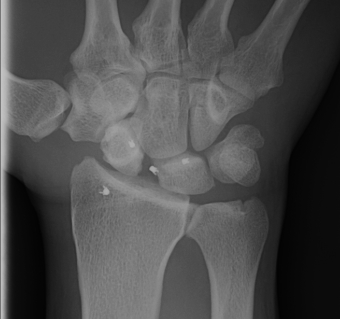

AP

Terry Thomas sign

- increased scapholunate interval

- > 3 mm compared with other side

Stress views

- bilateral wrists clenched

- in ulnar deviation

- in radial deviation

- may show Terry Thomas sign

Cortical Ring sign

- end-on view of cortex of distal pole of scaphoid

Scaphoid shortened

- due to palmar flexion